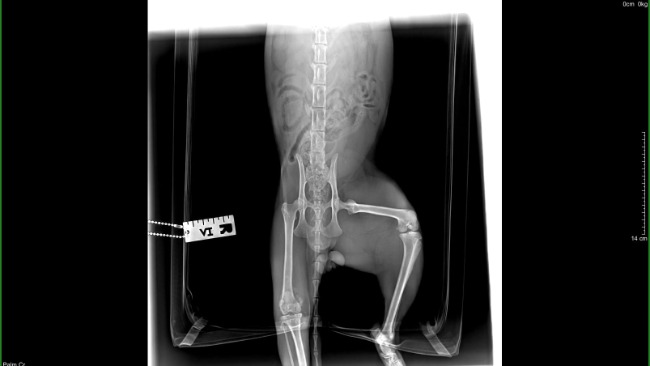

Oto wczorajsze podsumowanie wizyty w lecznicy. Brutusek odpoczywa, troche obrażony ze musi siedzieć zamknięty w klatce. Niestety łapkę trzeba oszczędzać, więc trochę tam posiedzi. Zrekompensujemy mu niewygodę smaczkami 😉 Może da się obłaskawić..

Cześć. Nazywam się Brutus. To powyżej jest moim pierwszym zdjęciem. Tam żyłem. Uszkodziłem sobie łapkę (w sumie nie sam, tylko ktoś mi pomógł). I trafiłem do weterynarza. Wyleczono mnie (koci katar) wykastrowano, jednakże z łapką mam dalej problem- zerwane więzadła. Czeka mnie operacja.. Boję się.Jestem niesamowitym miziakiem, już prawie miałem dom.. ale operacja pokrzyżowała mi plany. Musze uzbierać na zabieg. Pomożesz mi?